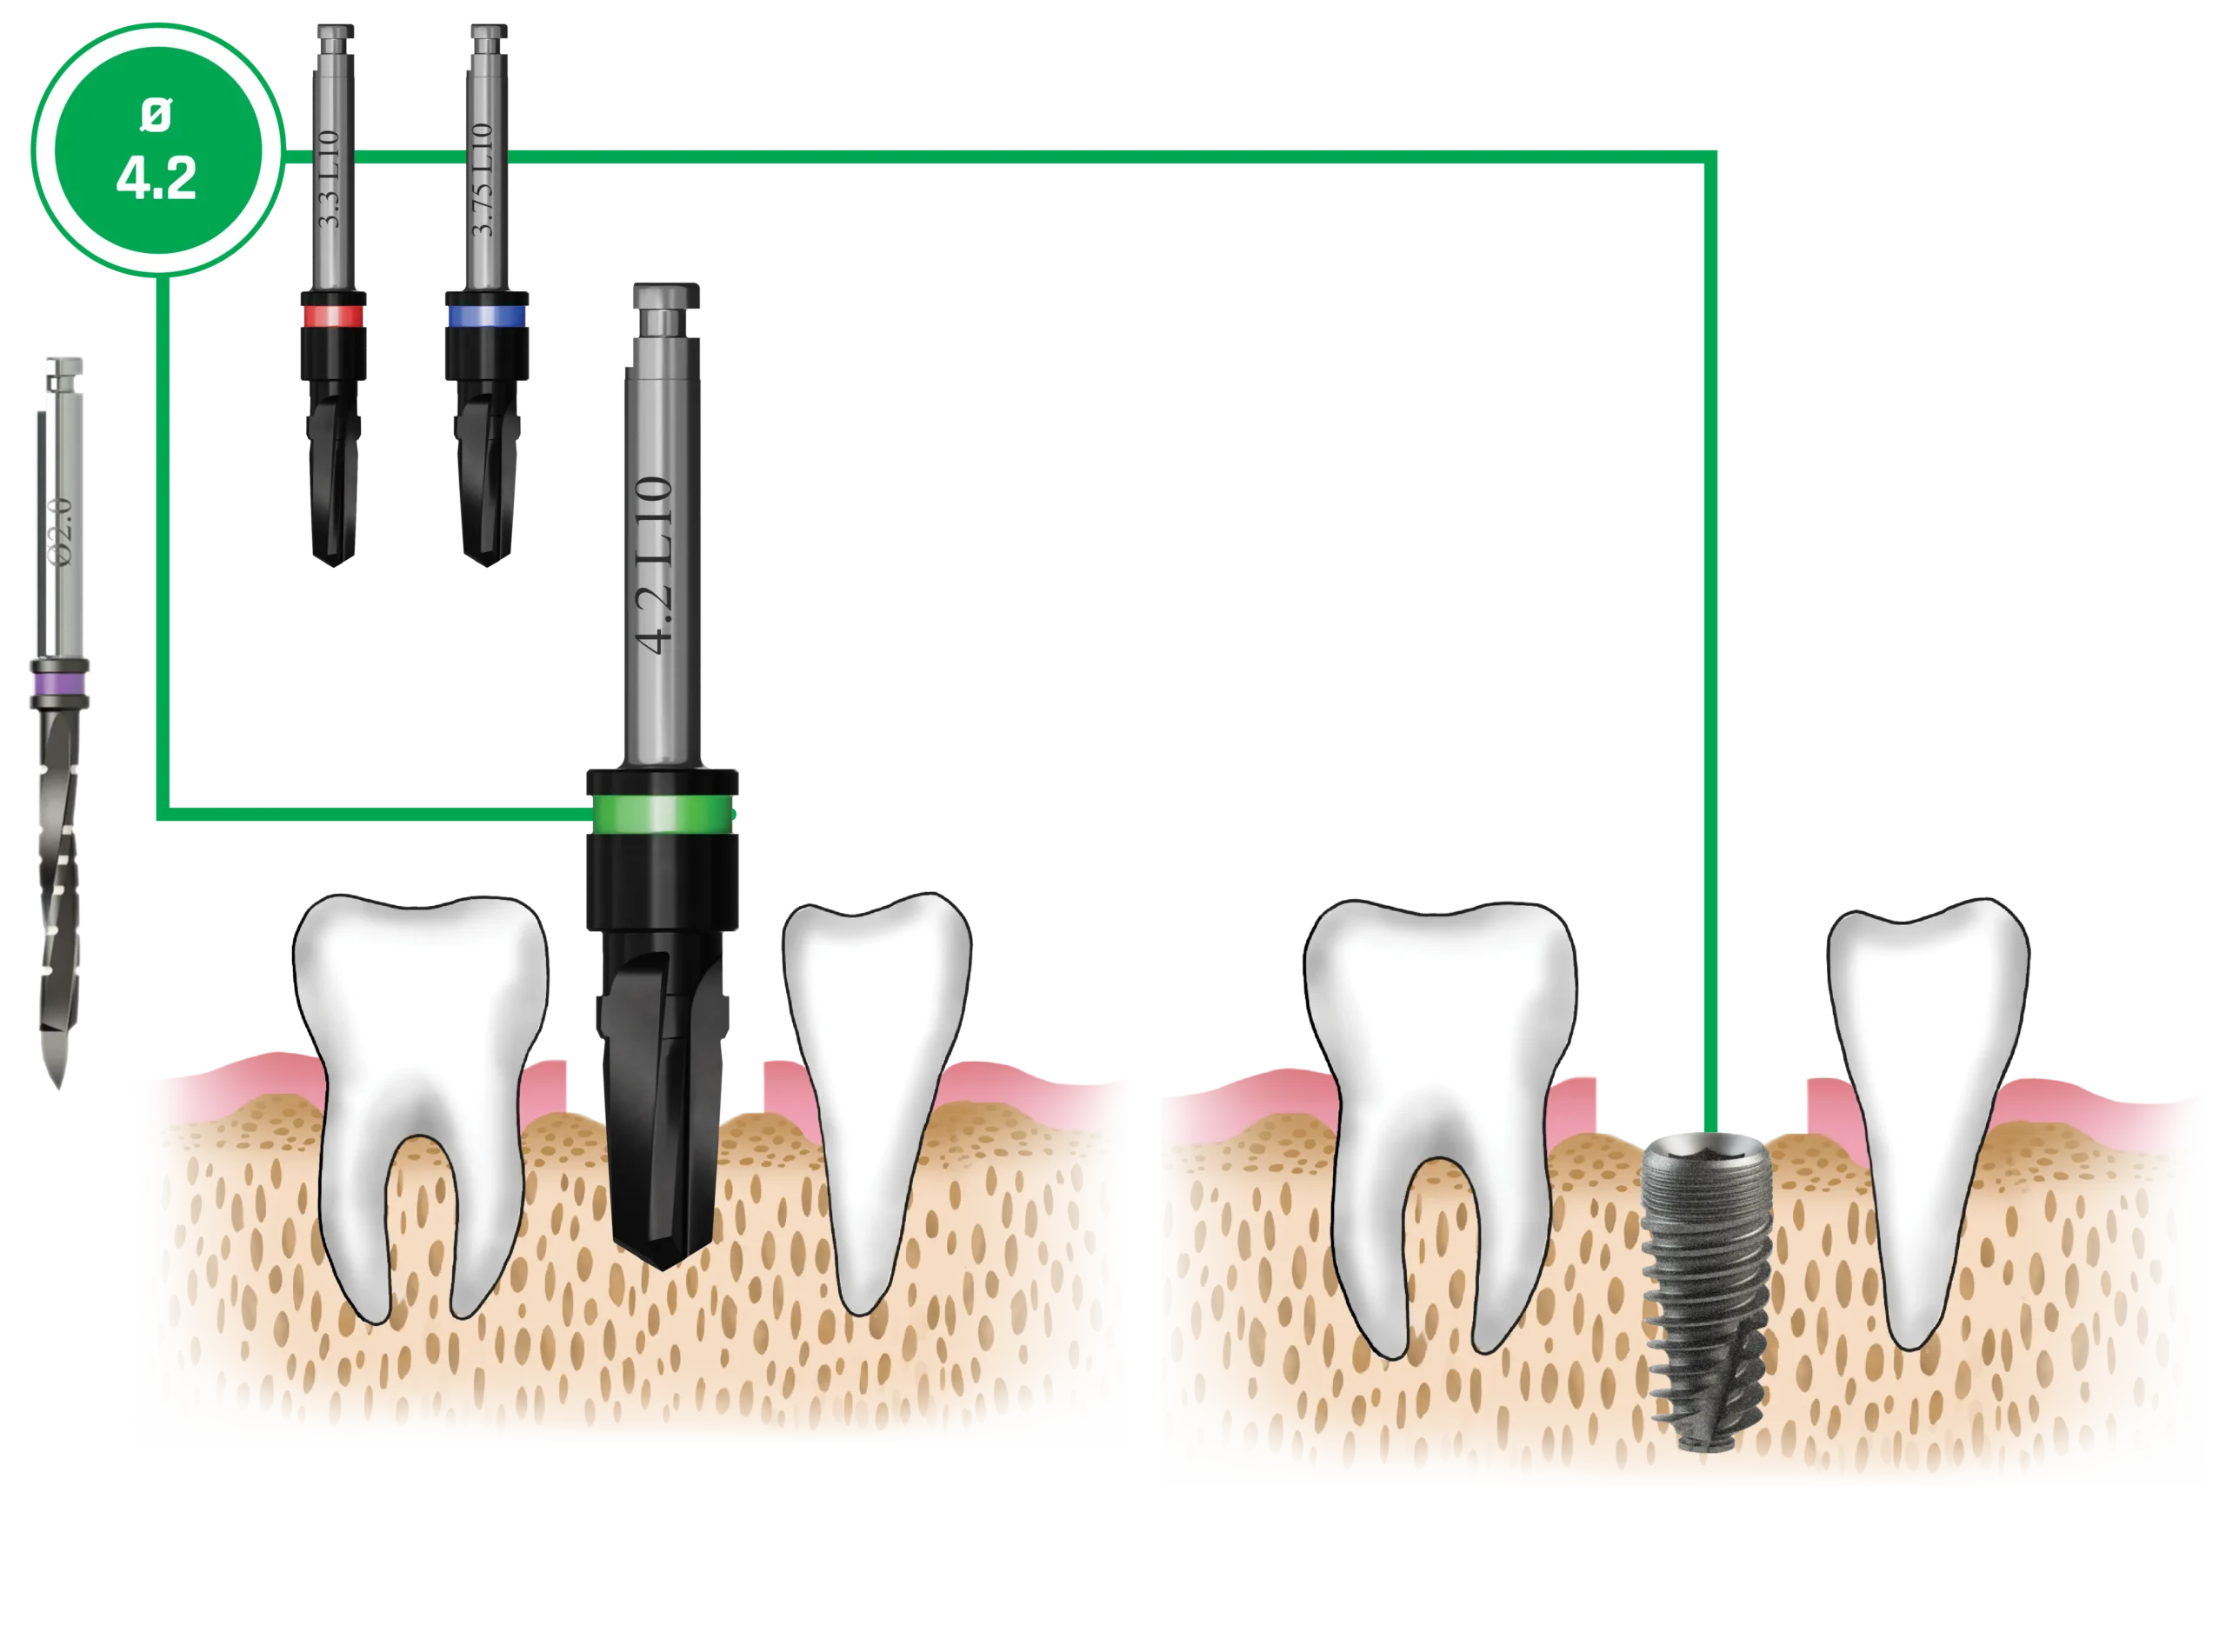

Quy trình mũi khoan

Nên sử dụng mũi khoan mồi 2.0 mm cho tất cả các đường kính implant. Các implant có đường kính 3.0 mm và 3.3 mm (Dòng Hẹp – Narrow Line) cùng với implant đường kính 3.75 mm (Dòng Tiêu Chuẩn – Standard Platform) nên được đặt ngang mức đỉnh xương. Các implant đường kính 4.2 mm, 5.0 mm và 6.0 mm (Dòng Tiêu Chuẩn – Standard Platform) có thể được đặt dưới mức đỉnh xương